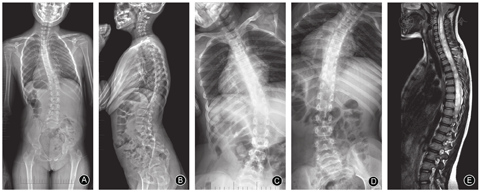

儿童组的主弯Cobb角为31.1°±11.9°(图3)、青少年组为56.7°±17.0°(图4)、成人组为70.7°±22.6°(图5),随着年龄增加,主弯Cobb角明显增大,三组的差异有统计意义(P< 0.001,表2);主弯柔韧性明显降低(63.9%±28.7% vs 43.8%±20.0% vs 36.9±22.7%,P=0.044,表2);次弯Cobb角明显增大(16.8°±8.8° vs 34.8°±14.7° vs 41.6°±17.2°,P< 0.001,表2)。

青少年组CB为(9.9±7.5)mm,优于儿童组(15.6±13.3)mm和成人组(18.7±14.9)mm(P=0.007,表2)。三组发生冠状面失衡的患者分别为2例、1例和3例。各组间主弯AVT的差异则无统计学意义(P=0.192,表2)。

儿童组、青少年组和成人组患者的TK(32.1°±8.0° vs 32.5°±12.9° vs 43.3°±20.9°,P=0.017,表3)、LL(50.4°±9.3° vs 54.6°±13.1° vs 63.4°±16.3°,P=0.013,表3)、PI(32.1°±10.2° vs 42.7°±10.1° vs 44.1°±9.9°,P=0.006,表3)和PT(-1.9°±12.3° vs 4.9°±8.1° vs 5.8°±7.1°,P=0.045,表3)随着年龄的增加而增大。三组SS(P=0.444,表3)和SVA(P=0.742,表3)的差异则无统计学意义,发生矢状面失衡的患者分别为0例、3例和1例。

本研究是首个关于CMI伴脊柱侧凸患者自然史的横断研究,比较儿童组(图2)、青少年组(图3)和成人组(图4)三个不同年龄段患者的影像学特征。结果显示三组患者的非典型弯发生率较高,且各组间弯型分布的差异无统计学意义,这与既往文献报道的结果一致[11,25];随着年龄的增长,患者主弯和次弯Cobb角增大,而主弯柔韧性下降,此结果符合临床经验,与特发性脊柱侧凸相似[26]。此外,有文献报道接受支具或手术治疗的CMI患者,年龄≥10.5岁、Cobb角≥44.5°是侧凸进展的强预测因子[27]。青少年组的CB明显优于另外两组,可能预示着随着年龄增长,CMI患者的冠状面是由失衡到平衡,再到失衡的动态过程,此结果有待于进一步验证。矢状面X线片显示年龄越大的CMI患者,TK、LL、PI和PT均明显增大,这一变化趋势符合正常中国成年人群脊柱和骨盆的矢状面参数[22];CMI患者与正常人群的对比在既往文献中也有报道[28]。